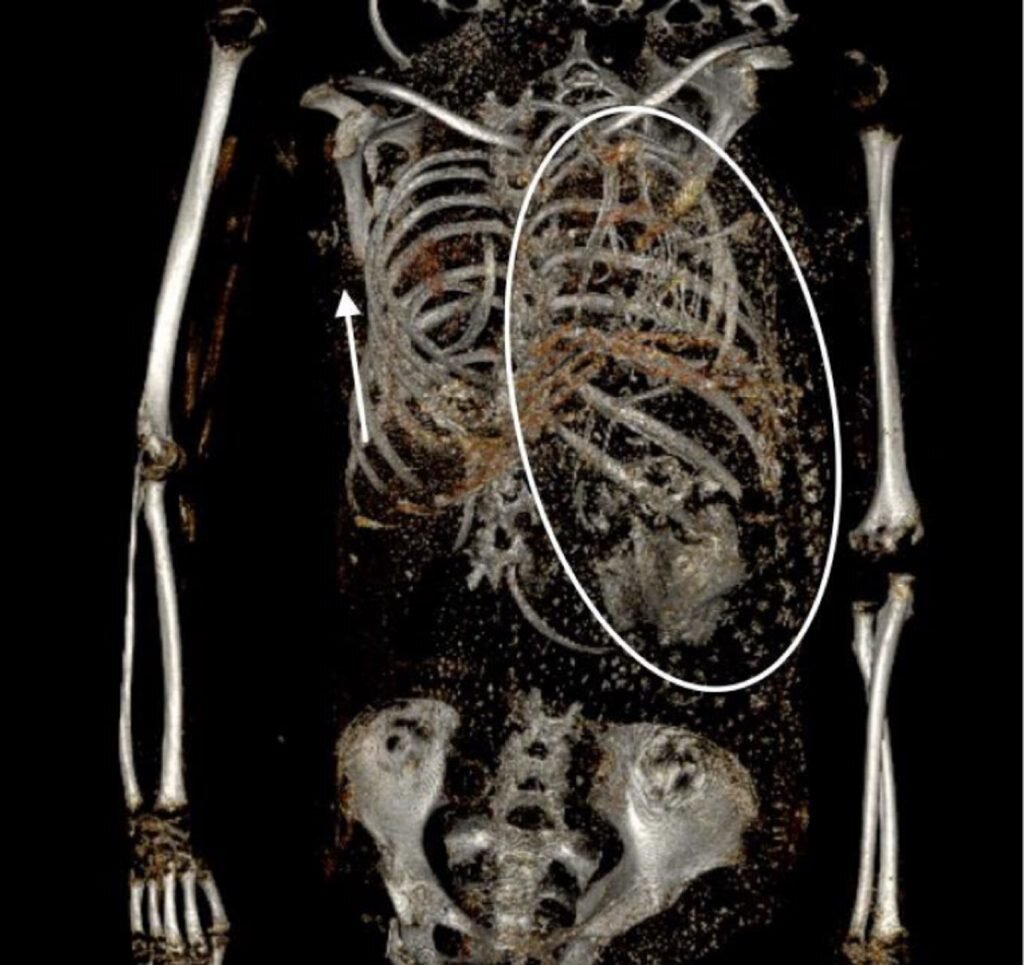

Останки второго плода в грудной клетке матери. Фотографии: Francine Margolis, David R. Hunt, International Journal of Ostearchaeology

Используя компьютерную томографию остеоархеологи повторно проанализировали необычную находку, чтобы разгадать детали этого кровавого инцидента. Вопреки исходным предположениям о странном кровавом ритуале сканирование показало наличие второго плода в грудной полости женщины. Более того в тазу матери ученые обнаружили оторванную голову второго младенца.